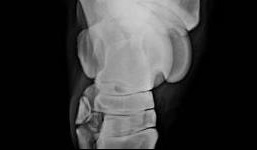

Afb. 1: 1. Gewrichtsknobbel (bot) 2. Gewrichtskom (bot) 3. Gewrichtssmeer (synoviaal vocht) 4. (Beschadigd) kraakbeen 5. Botuitsteeksel aan de randen van het gewrichtsvlak (osteofyt) 6. Gewrichtskapsel 7. Gewrichtsbanden